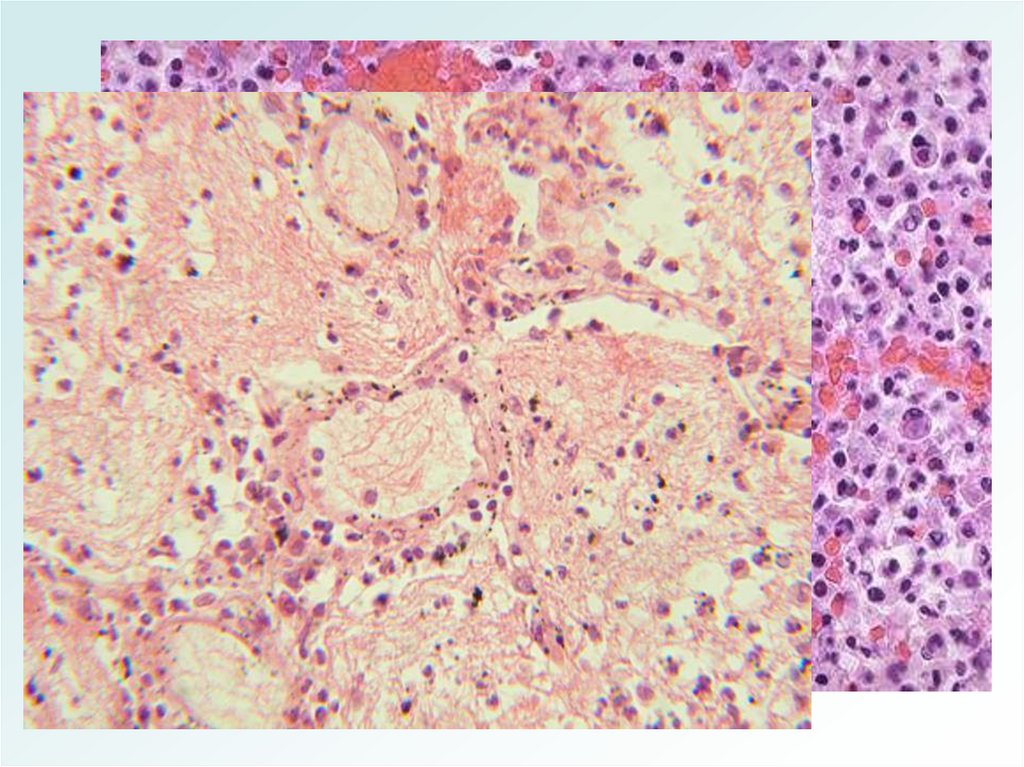

Бронхопневмония (очаговая)

• Составляет 62-70% острых пневмоний.

• Чаще - вторичная, самостоятельным

заболеванием является только у детей

раннего возраста и лиц пожилого и

старческого возраста.

• Полиэтиологична.

• Возникает на фоне снижения иммунитета.

МОРФОЛОГИЯ

БРОНХОПНЕВМОНИИ

1.Очаговое воспаление (бронхиолит +

альвеолит)

2.Эмфизема

3.Ателектаз